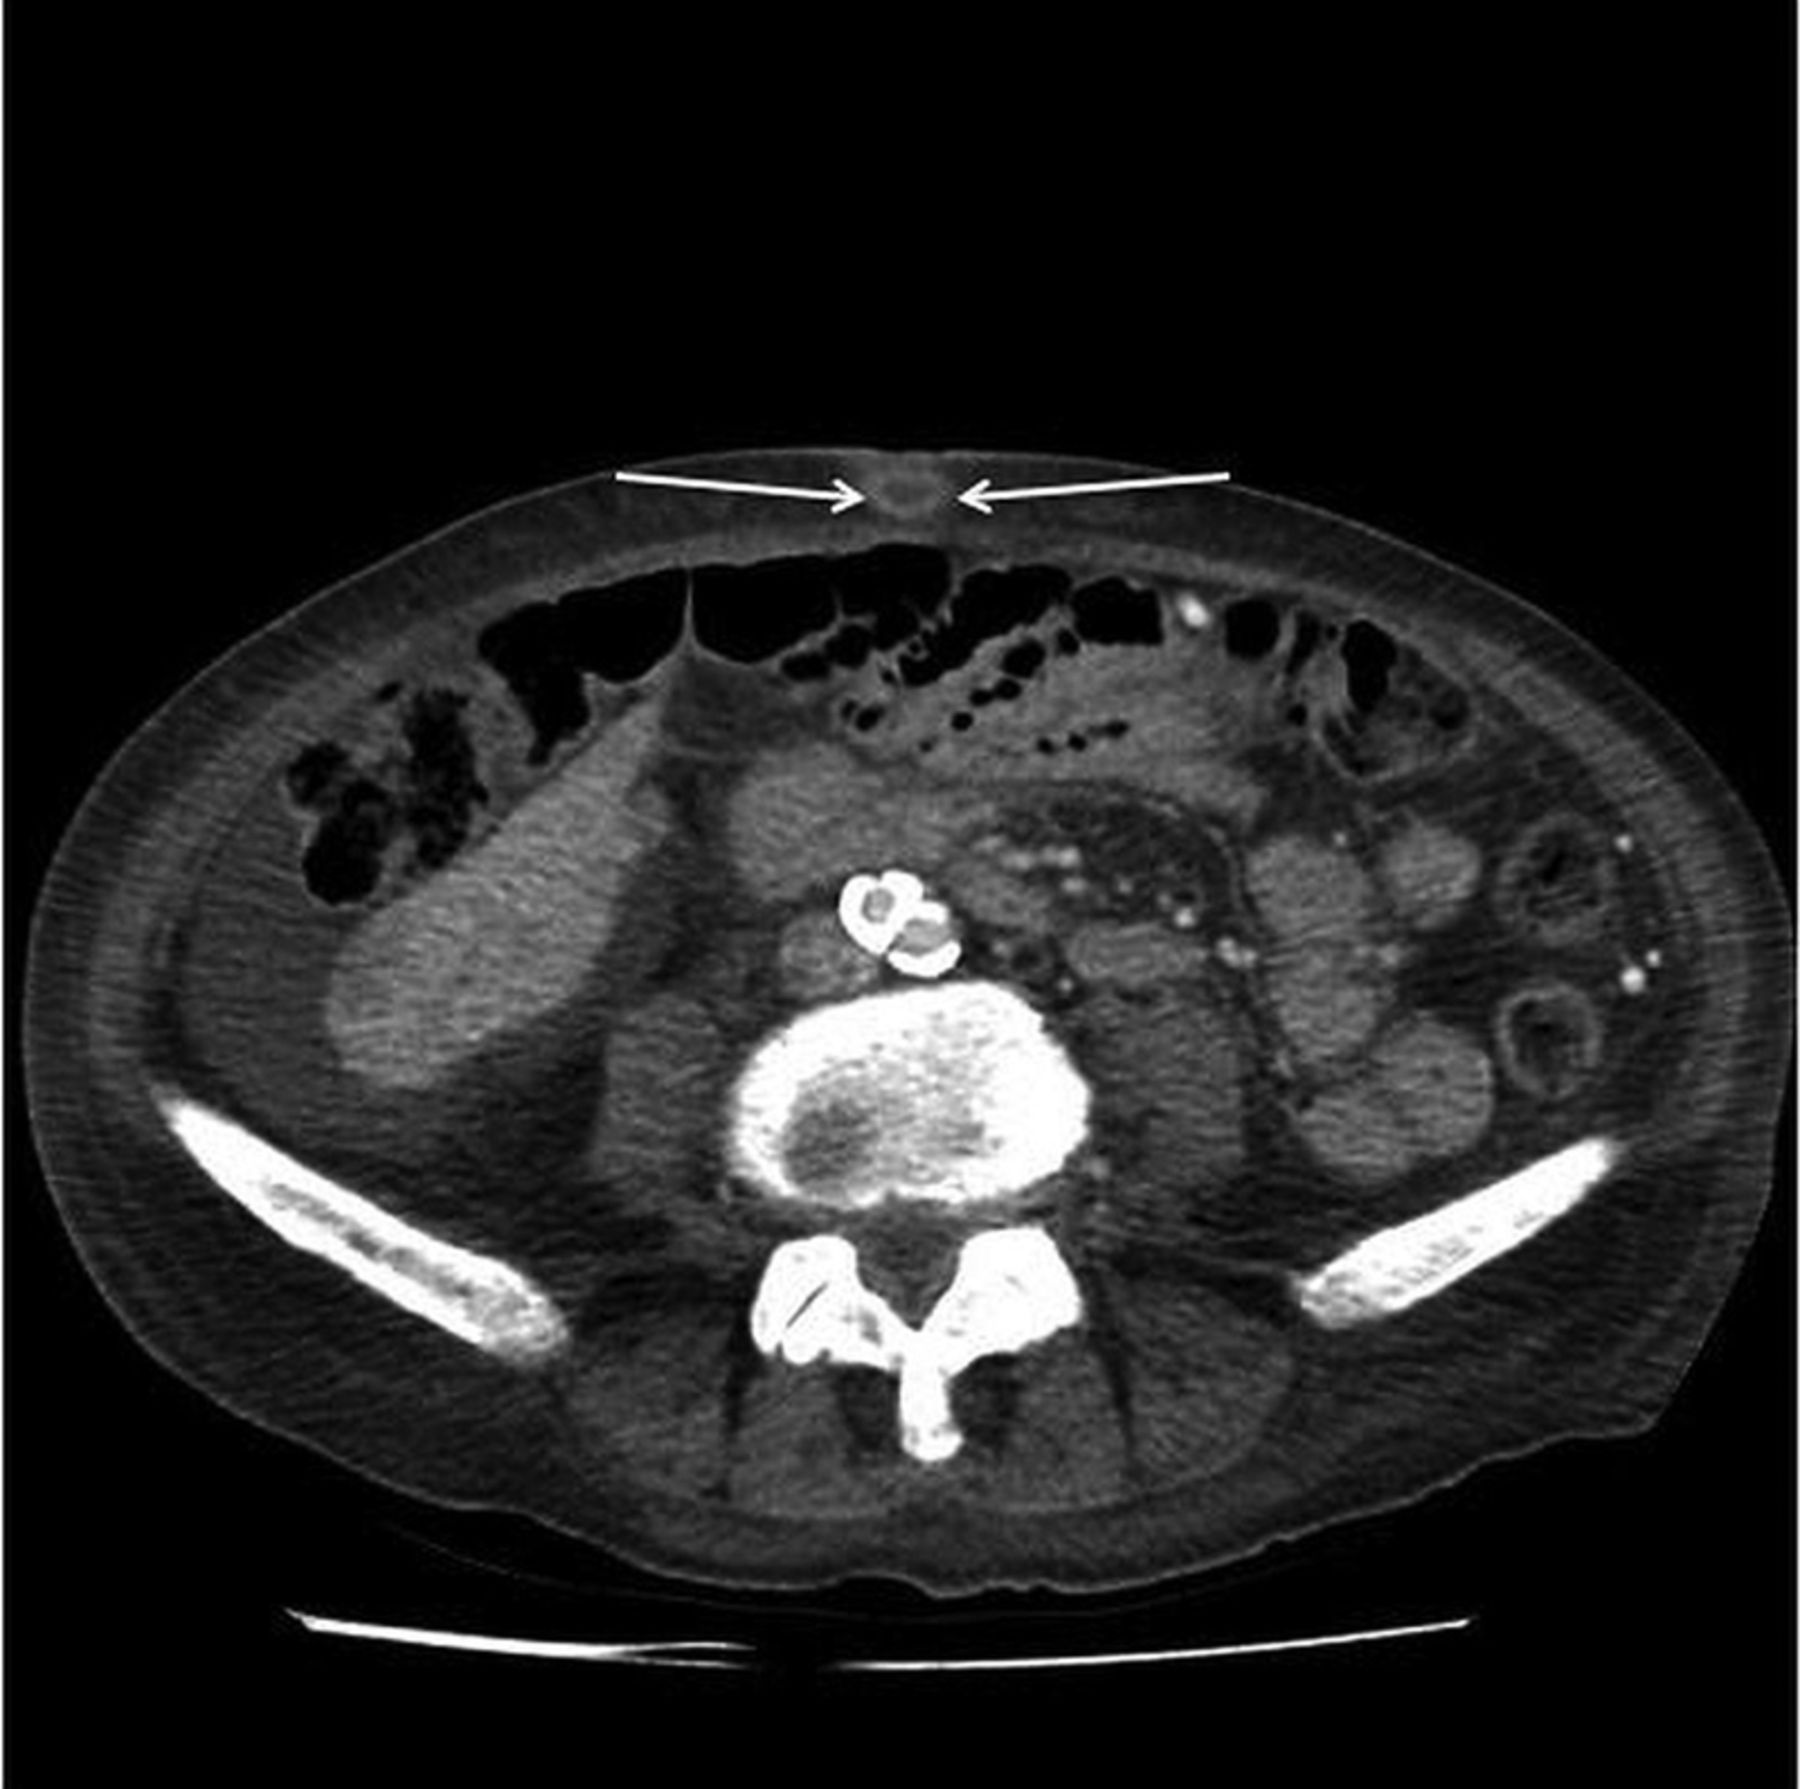

Learn about the Sister Mary Joseph sign, a rare clinical finding indicating metastatic abdominal or pelvic malignancy. Discover how this umbilical nodule serves as a vital diagnostic marker for advanced cancer, its underlying pathophysiology, and why identifying this physical sign is critical for prompt oncology evaluation and effective patient care planning.